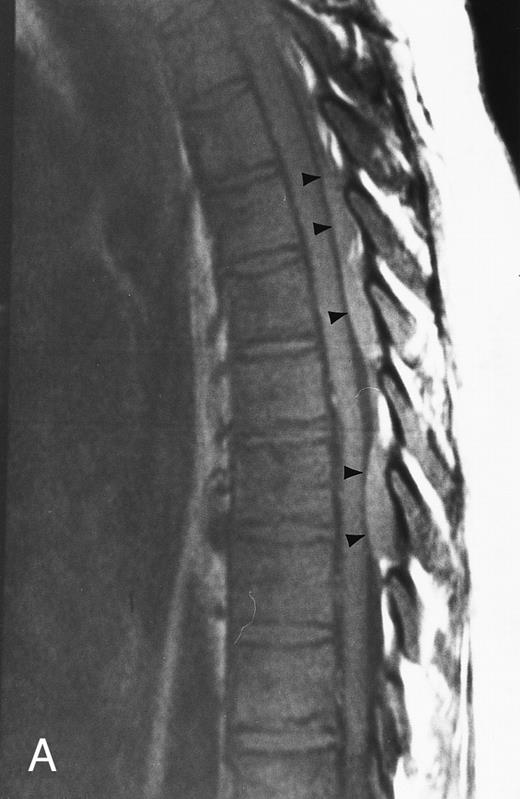

T1-weighted (500/11, TR/TE) sagittal MR images of the lumbosacral spine in a 45-year-old woman before (A) and 40 days after (B) bone marrow transplantation for multiple myeloma. There is a diffuse MR pattern of marrow involvement in (A) (bone marrow plasma cells, 50%; monoclonal protein, 6.0 g/dL). On the posttreatment image, there is definite reinstitution of fatty marrow in the spine and, in particular, around the basivertebral veins, in keeping with partial response to treatment (bone marrow plasma cells, 0.5%; monoclonal protein, 1.6 g/dL).